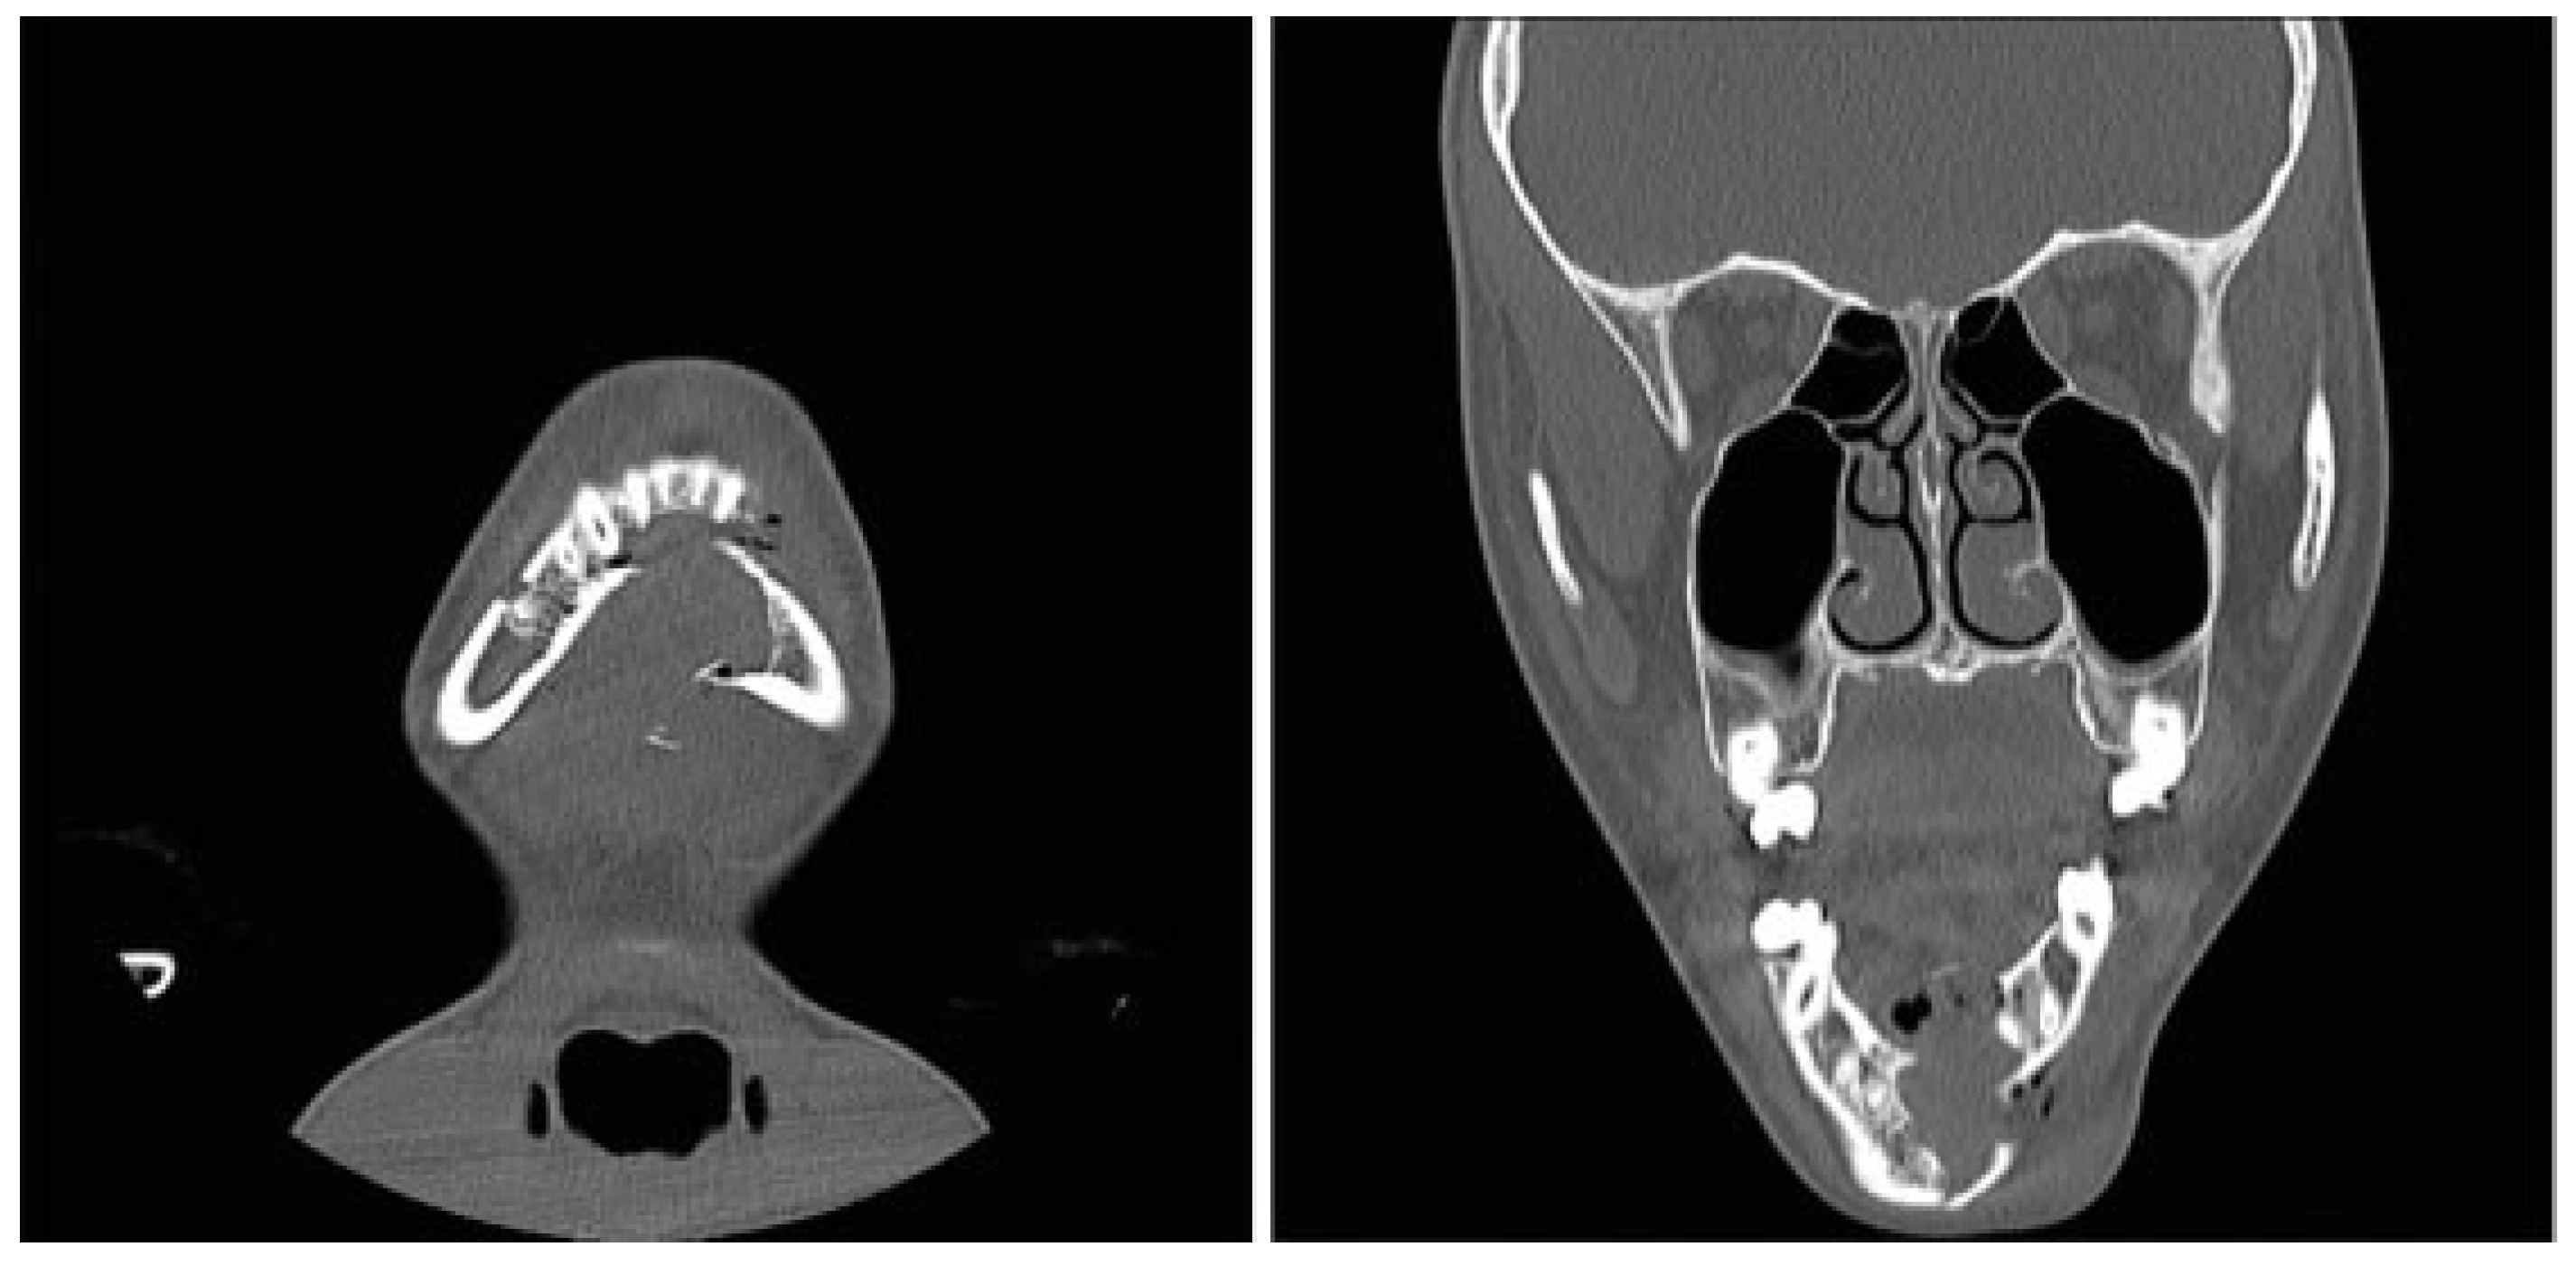

The Otolaryngology-Head and Neck Surgery department was consulted upon arrival to our ED. Physical examination revealed tenderness of the left side of the mandible and a visible intraoral step-off between the left mandibular lateral incisor and canine tooth. The CT was reviewed and demon- strated a significantly displaced fracture of the left para- symphysis. The fracture was deemed pathologic secondary to an apparent preexistent cystic lesion of the mandibular symphysis measuring 2.5 × 1.5 × 1.5 cm, with evidence of bony expansion (Figure 1).

Figure 1.

Coronal computed tomography (CT) scan revealing a parasymphyseal fracture in line with a cystic cavity.